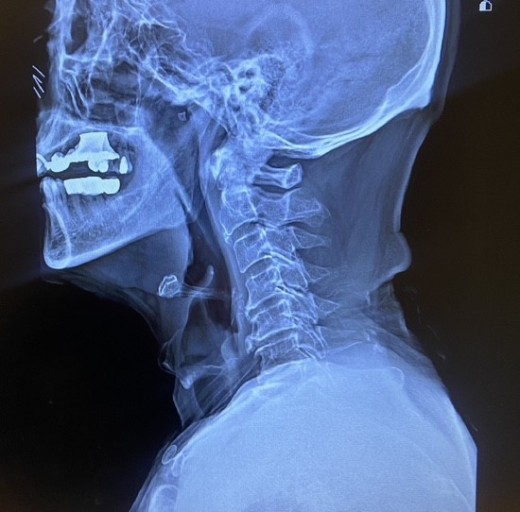

외부로부터 강력한 충격은 주로 교통사고로 인해서 발생돼요. 교통사고만 나면 주로 목을 잡게 되죠? 뒤차에 받혔을 때 주로 경추에 충격을 주어 주로 경추염좌 진단을 받는데 가벼운 증상일 때 빨리 치료를 해야 되므로 입원해서 치료를 받는 게 좋다. 퇴형성으로 목 디스크 증상이 조금씩은 다 있는데 이럴 때 교통사고 나면 전문기관 가서 X-Ray 촬영하다 보면 디스크(경주 염좌) 진단을 받게 됩니다.

우리의 성인 기준 머리 무게는 약 5.5kg 정도이죠. 목을 앞으로 숙이는 잘못된 자세를 오랫동안 지속하다 보면 목 디스크 증상 발생의 원인이 돼요. 스마트폰의 장시간 사용하기 그리해서 많이 발생되고 또한 직업병으로 컴퓨터를 오래동안 사용하기 그리해서 목뼈의 C자형이 변해서 거북목처럼 변형되기도 합니다..